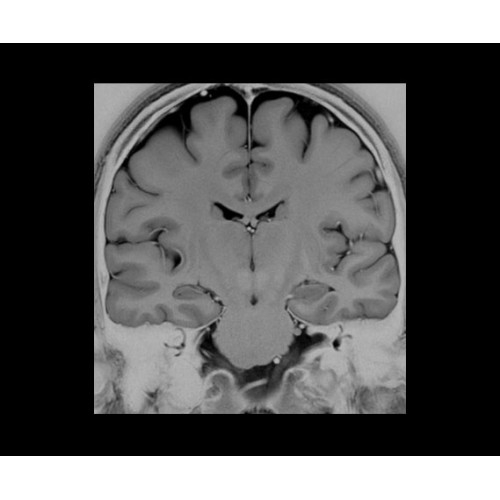

SIGNA Architect 3.0T — это новейший МРТ аппарат компании GE, который предлагает высочайший уровень производительности — в системе 128 приемных каналов, 48 канальная катушка головы, полный спектр клинических возможностей. Высокий уровень комфорта пациента обеспечивают такие особенности как отсоединяемый стол, положение пациента «ногами вперед» для всех видов исследований, SilentWorks — бесшумное и MAGIC — быстрое сканирование.

Теперь возможности МРТ поражают еще больше благодаря ультрасовременным решениям для визуализации с SIGNA Architect 3.0 Тл, объединяющей новейшие достижения в области МР-технологий и интуитивно понятный интерфейс. Система SIGNA Architect, разработанная на базе новой платформы SIGNA Works, представляет собой гармоничное сочетание дизайна и функциональности. Каждый элемент системы направлен на повышение производительности, эффективности клинической практики, финансовых показателей, а также комфорта и безопасности пациента.

Поле обзора 50x50x50 см и апертура шириной 70 см позволят достоверно визуализировать сложные анатомические области для пациентов с крупным телосложением, например, плечи и бедра. Феноменальная однородность системы SIGNA Architect обеспечивает наиболее широкое поле обзора с улучшенными характеристиками градиентов. Ничто не останется незамеченным.

• NeuroWorks — универсальное решение для визуализации анатомии головного мозга, позвоночника, сосудов и периферических нервов с четкой дифференциацией тканей.

• 48-канальная катушка TDI для головы, входящая в базовую комплектацию SIGNA Architect, обеспечивает феноменальную производительность с учетом особенностей каждого пациента. Благодаря гибкому и универсальному дизайну, высокому соотношению сигнал/шум и передовым технологиям визуализации, таким как HyperWorks, учитываются потребности подавляющего большинства пациентов.